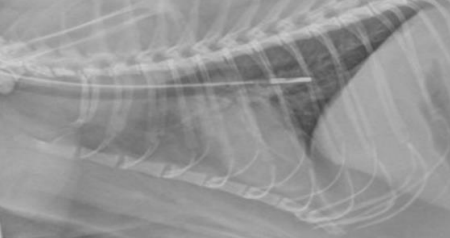

What technique is done with a syringe to ensure that a nasoesophageal/nasogastric tube is placed correctly? If it is negative, it is in the esophagus, if there is air and liquid, it is in the stomach, and if there is only air, it is in the trachea. X-rays (L-L) and injection of 3-5 ml sterile saline/water for injection not under sedation can also be done for confirmation.